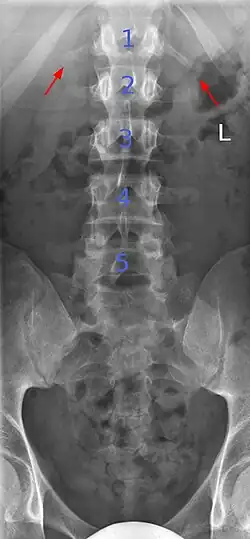

Short ribs at the first lumbar vertebra, which is thus a transitional vertebra, since lumbar vertebrae normally do not have ribs attached to them.

Transitional vertebrae have the characteristics of two types of vertebra. The condition usually involves the vertebral arch or transverse processes. It occurs at the cervicothoracic, thoracolumbar, or lumbosacral junction. For instance, the transverse process of the last cervical vertebra may resemble a rib. A transitional vertebra at the lumbosacral junction can cause arthritis, disk changes, or thecal sac compression. Back pain associated with lumbosacral transitional vertebrae (LSTV) is known as Bertolotti's syndrome. One study found that male German Shepherd Dogs with a lumbosacral transitional vertebra are at greater risk for cauda equina syndrome, which can cause rear limb weakness and incontinence.[11]

The significance of transitional vertebrae has been questioned by one study finding similar prevalence in the general population as those with low back pain, [12] but more recent study found a large difference.[13]